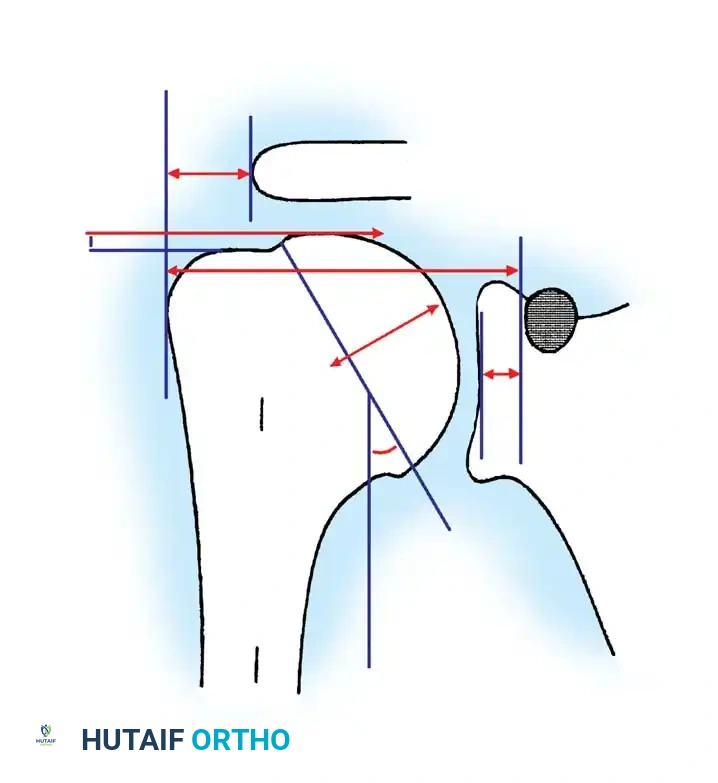

Anatomy and Biomechanics of the Glenohumeral Joint

A profound understanding of glenohumeral geometry is paramount for successful arthroplasty. The articular surface of the humeral head is essentially spherical, encompassing an arc of approximately 160 degrees.

Key Anatomical Parameters (Table 8-1):

* Radius of Curvature: The humeral head radius is approximately 25 mm. The glenoid articular surface radius is intentionally mismatched, being 2 to 3 mm larger than the humeral head to allow for translation and reduce edge loading.

* Neck-Shaft Angle (Inclination): Averages 45 degrees (± 5 degrees) relative to the diaphysis, though arthritic shoulders often present with a flatter angle closer to 50 degrees.

* Retroversion: Highly variable among individuals, ranging from 0 to 55 degrees depending on the measurement axis (e.g., epicondylar axis vs. forearm). Average glenoid version is 1.5 degrees of retroversion.

* Humeral Offset: The medial offset ranges from 4 to 14 mm, and the anteroposterior offset ranges from -2 to 10 mm.

Surgical Warning: Biomechanical studies demonstrate that shoulder kinematics are severely compromised if the prosthetic head is too thick, too thin, or shifted from the anatomical neck plane. Increasing humeral head thickness by just 5 mm can reduce glenohumeral range of motion by 20 to 30 degrees due to overstuffing the joint. The prosthetic head must be within 4 mm of the original head thickness.